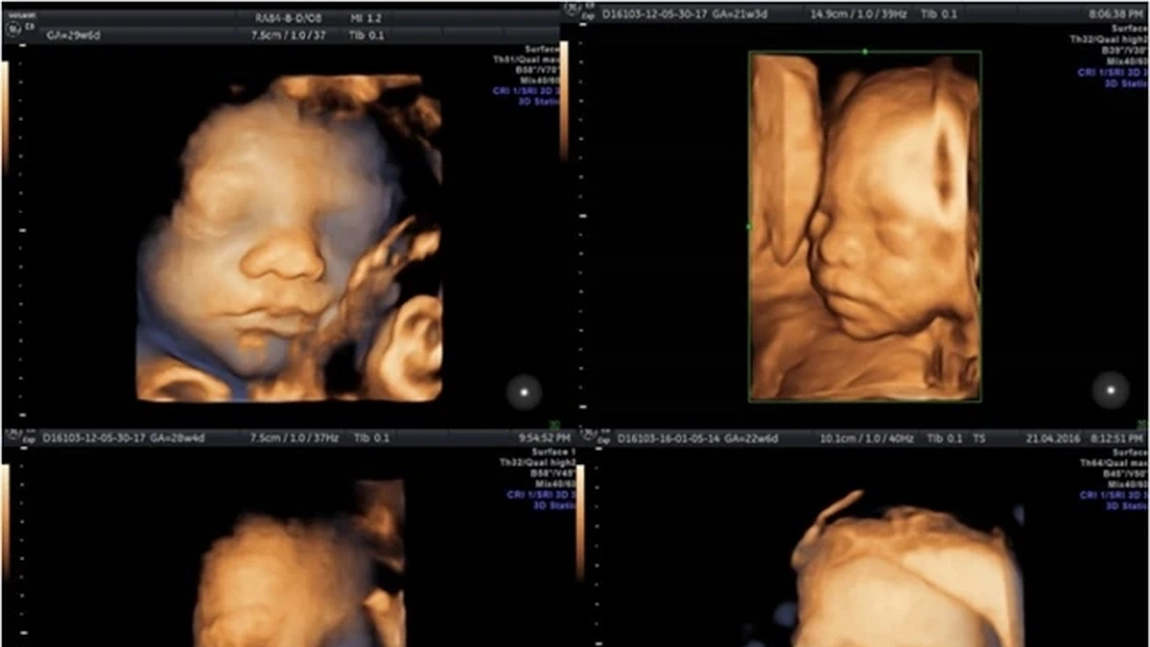

Morfologia fetală din trimestrul al doilea se efectuează, de regulă, între săptămânile 20 și 24 de sarcină. În acest interval, organele fătului sunt suficient de dezvoltate pentru a putea fi analizate în detaliu. Conform Monza Ares, medicul evaluează structura creierului, inima, coloana vertebrală, rinichii, membrele, dar și placenta și lichidul amniotic.

”Prin examenul morfologic de trimestrul II (ecografie de nivel II-B) se efectuează biometria fetală şi se vizualizează în detaliu anatomia fetală. Se notează localizarea placentei, anomaliile de cordon sau lichid amniotic. La acest moment se apreciază riscul de naştere prematură prin măsurarea lungimii colului uterin”, a afirmat dr. Monica Titianu, medic primar Obstetrică-Ginecologie.

În majoritatea cazurilor, tariful acoperă examinarea completă a anatomiei fetale, măsurători biometrice, evaluarea placentei și a cordonului ombilical, precum și discuția cu medicul la finalul investigației. Unele pachete includ includ și imagini digitale sau acces online la rezultate. Dacă se optează pentru ecografie 3D/4D, costul poate fi separat sau inclus într-un pachet premium.